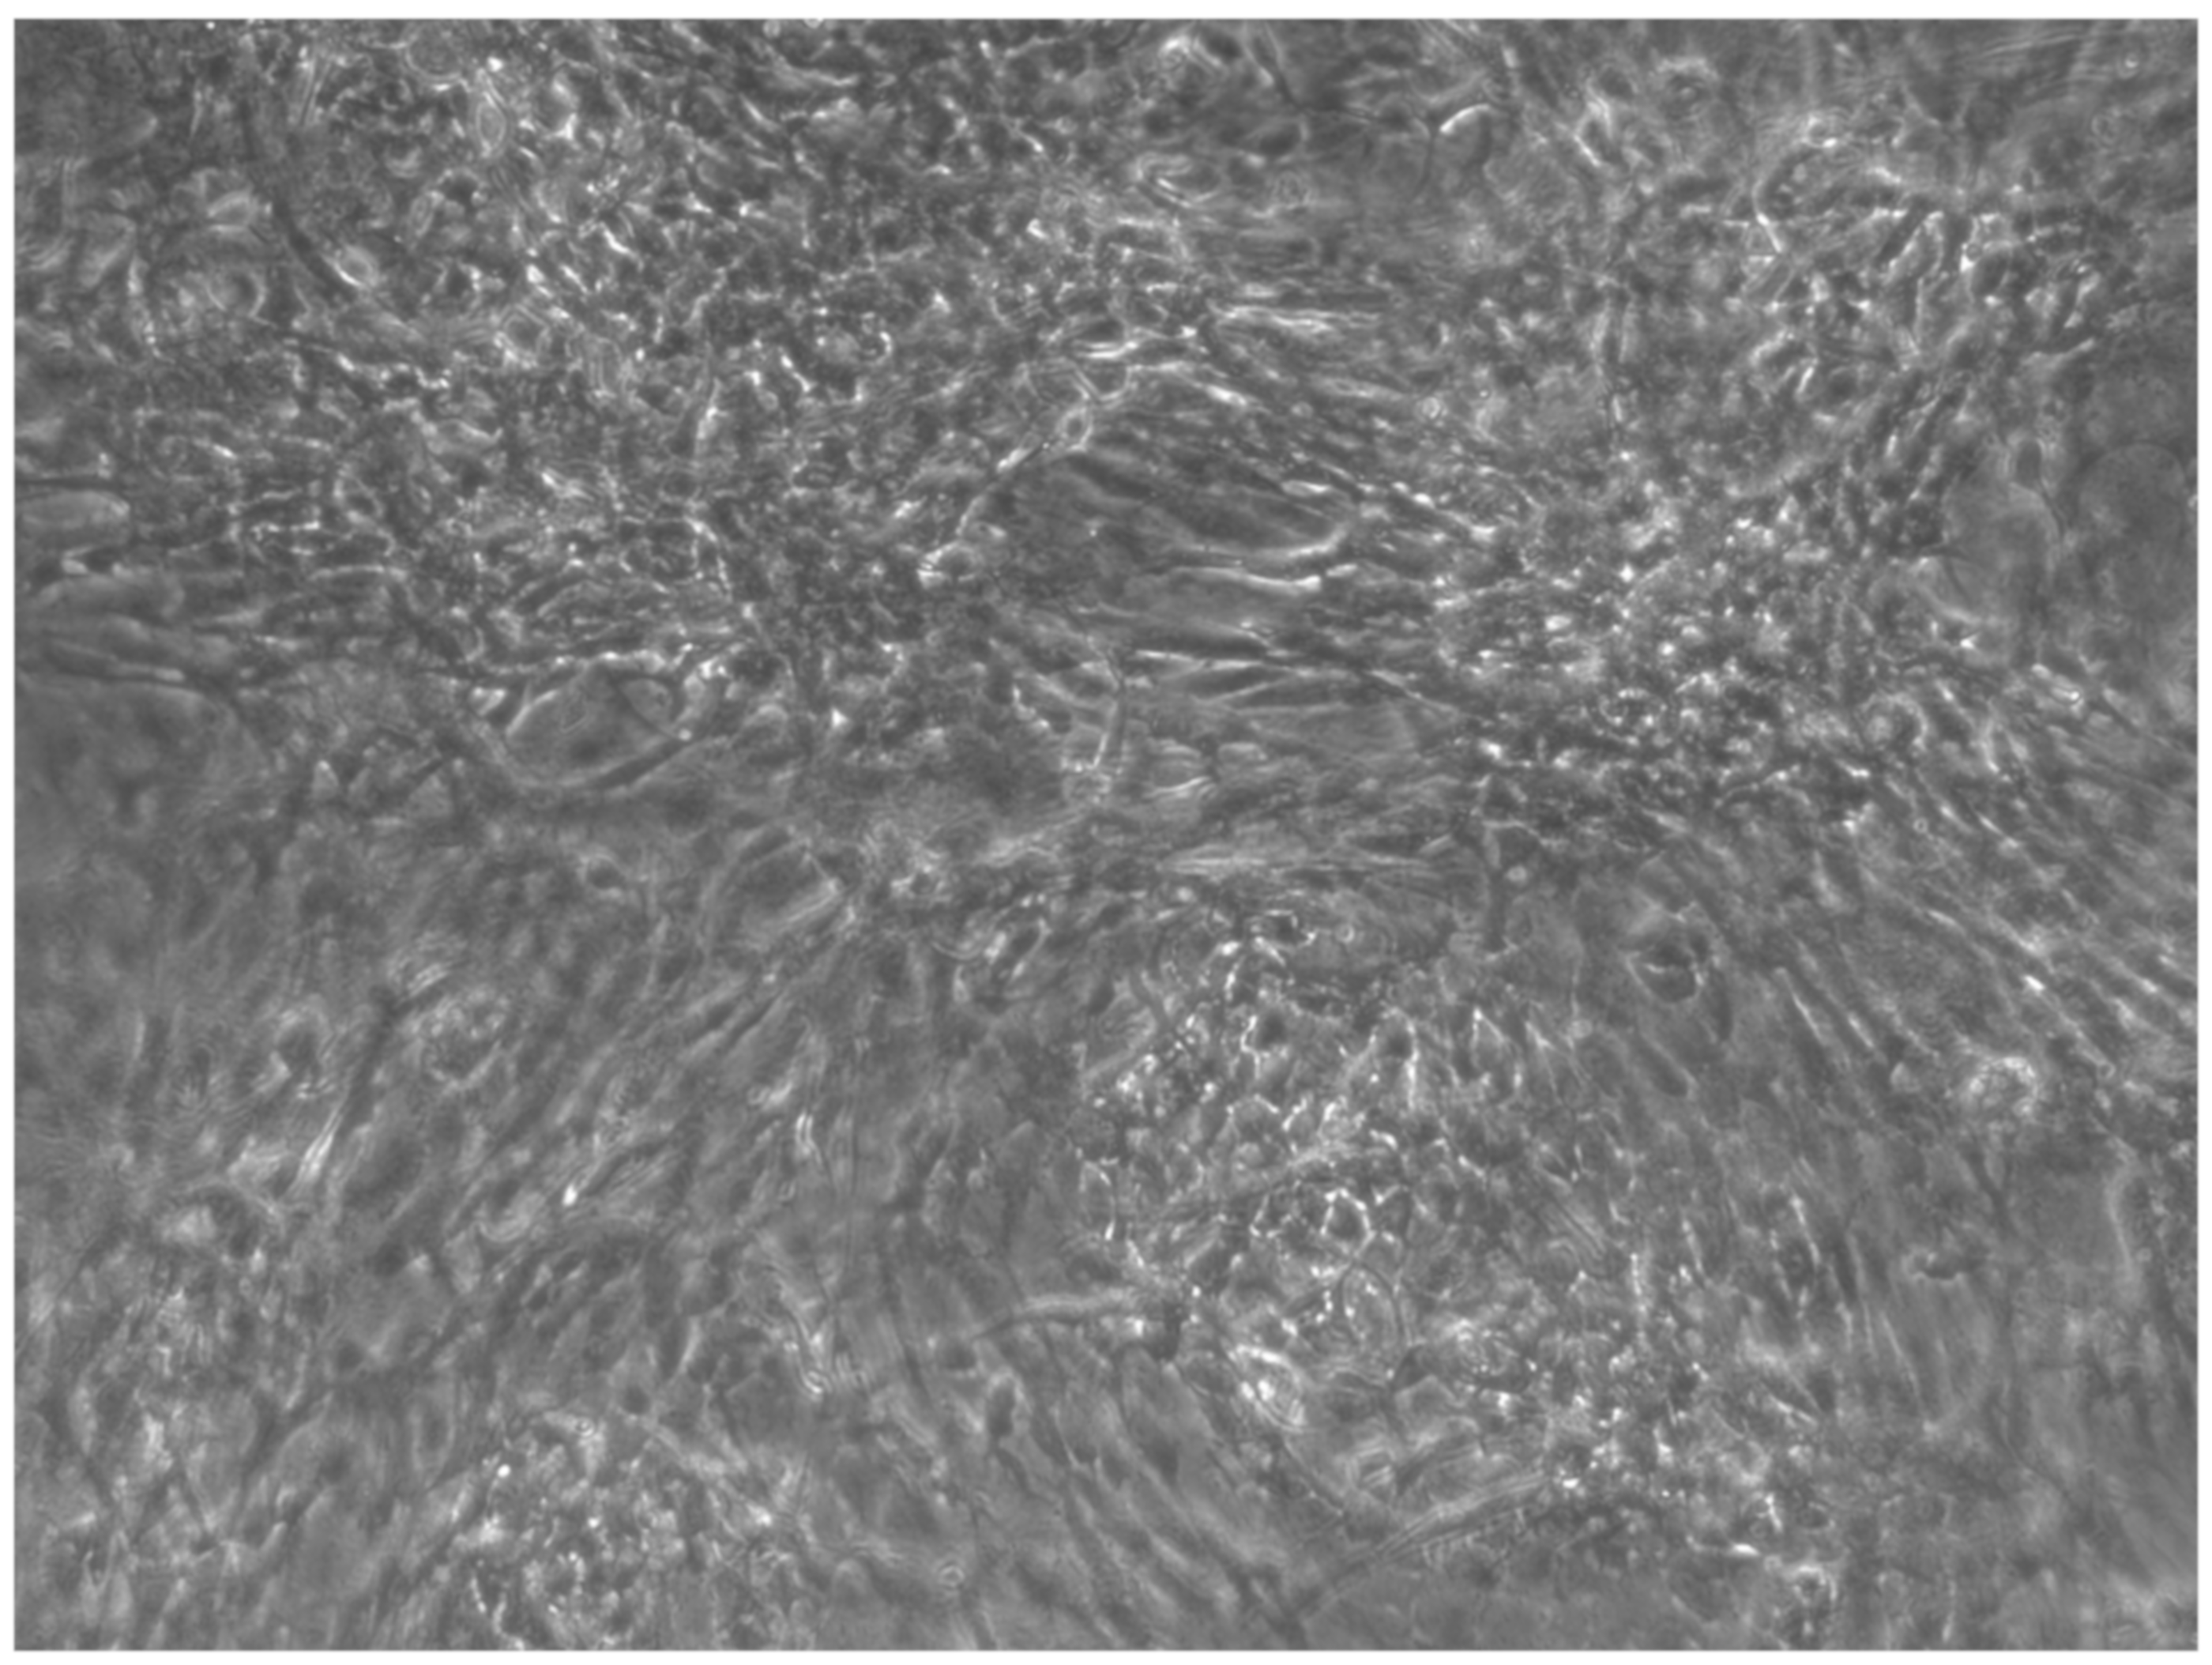

2.1. iPSC Reprogramming, Characterization, Validation of Pluripotency, and Multilineage Differentiation Potential

2.2. Differentiation iPSCs in Osteoblast Cells